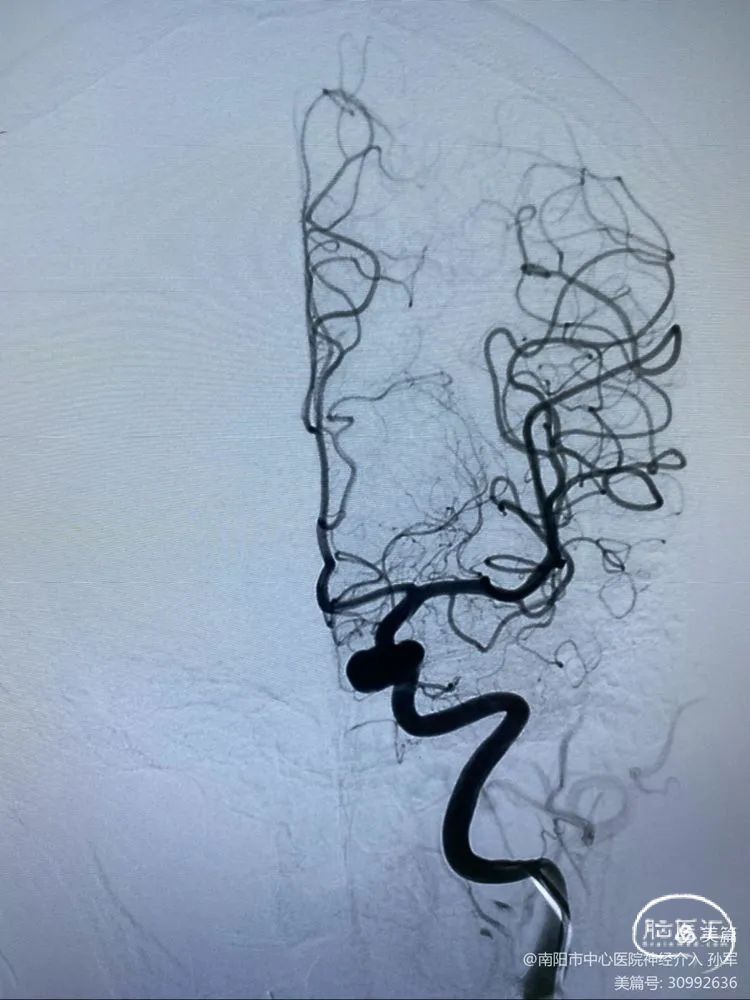

诊断:虹吸段大动脉瘤,瘤颈部分瘤化

手术计划:Pipeline Flex结合弹簧圈治疗

术前影像学资料